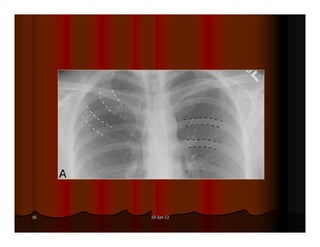

Được xem là hít đủ sâu khi ta thấy được hình chiếu của xương

sườn lên phổi 6 cung sườn trước hoặc 10 cung sườn sau.

Hít không đủ sâu Hít đủ sâu